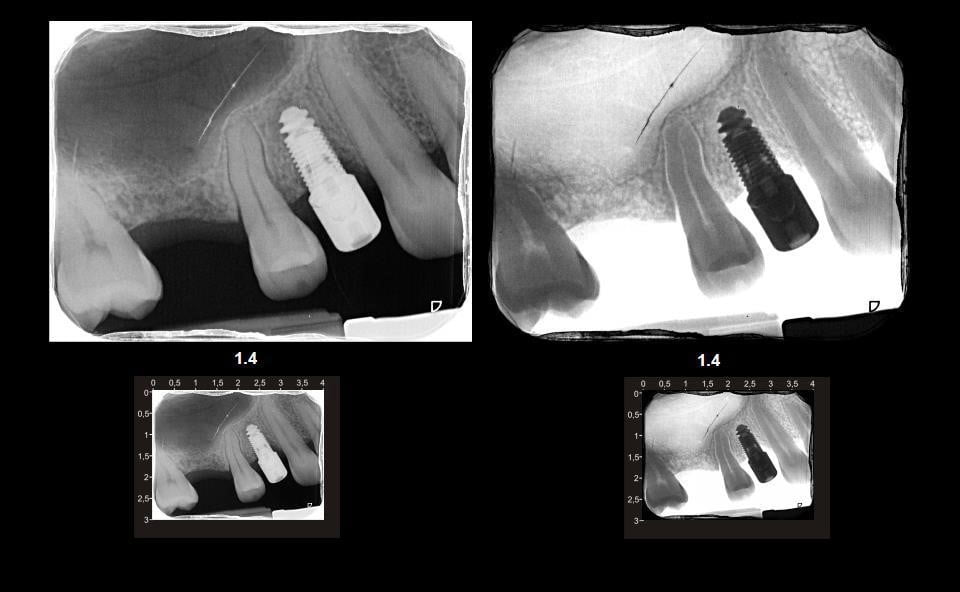

Mini-implanturile dentare sunt mai inguste decât implanturile obișnuite. Acestea sunt utilizate în anumite cazuri în locul implanturilor normale, din motive medicale, financiare sau anatomice. Cel mai frecvent sunt folosite pentru dinții mici, dinții din față, premolarii, dinții din zone înguste sau pentru pacienții la care densitatea țesutului osos este scăzută. Susținând majoritatea tipurilor de dinți de înlocuire, mini implanturile sunt folosite pentru proteze semimobile, punți și coroane fixe. Diferențele dintre mini-implanturi și implanturile obișnuite: Dimensiune – Diferența de dimensiune constă în diametrul implantului. Mini-implanturile dentare măsoară mai puțin de 3 mm în diametru, în timp ce implanturile obișnuite măsoară 3,5-5 mm. Rezistența – deoarece mini-implanturile sunt mai mici, nu pot suporta forța de masticatie pe care o poate suporta un implant obișnuit. Din acest motiv, acestea nu sunt folosite în cazul în care se înlocuiesc molarii. Procesul de vindecare – procesul de încorporare a unui mini-implant dentar este mai rapid decât cel al unui implant tradițional. Acest lucru este valabil și pentru timpul de vindecare.